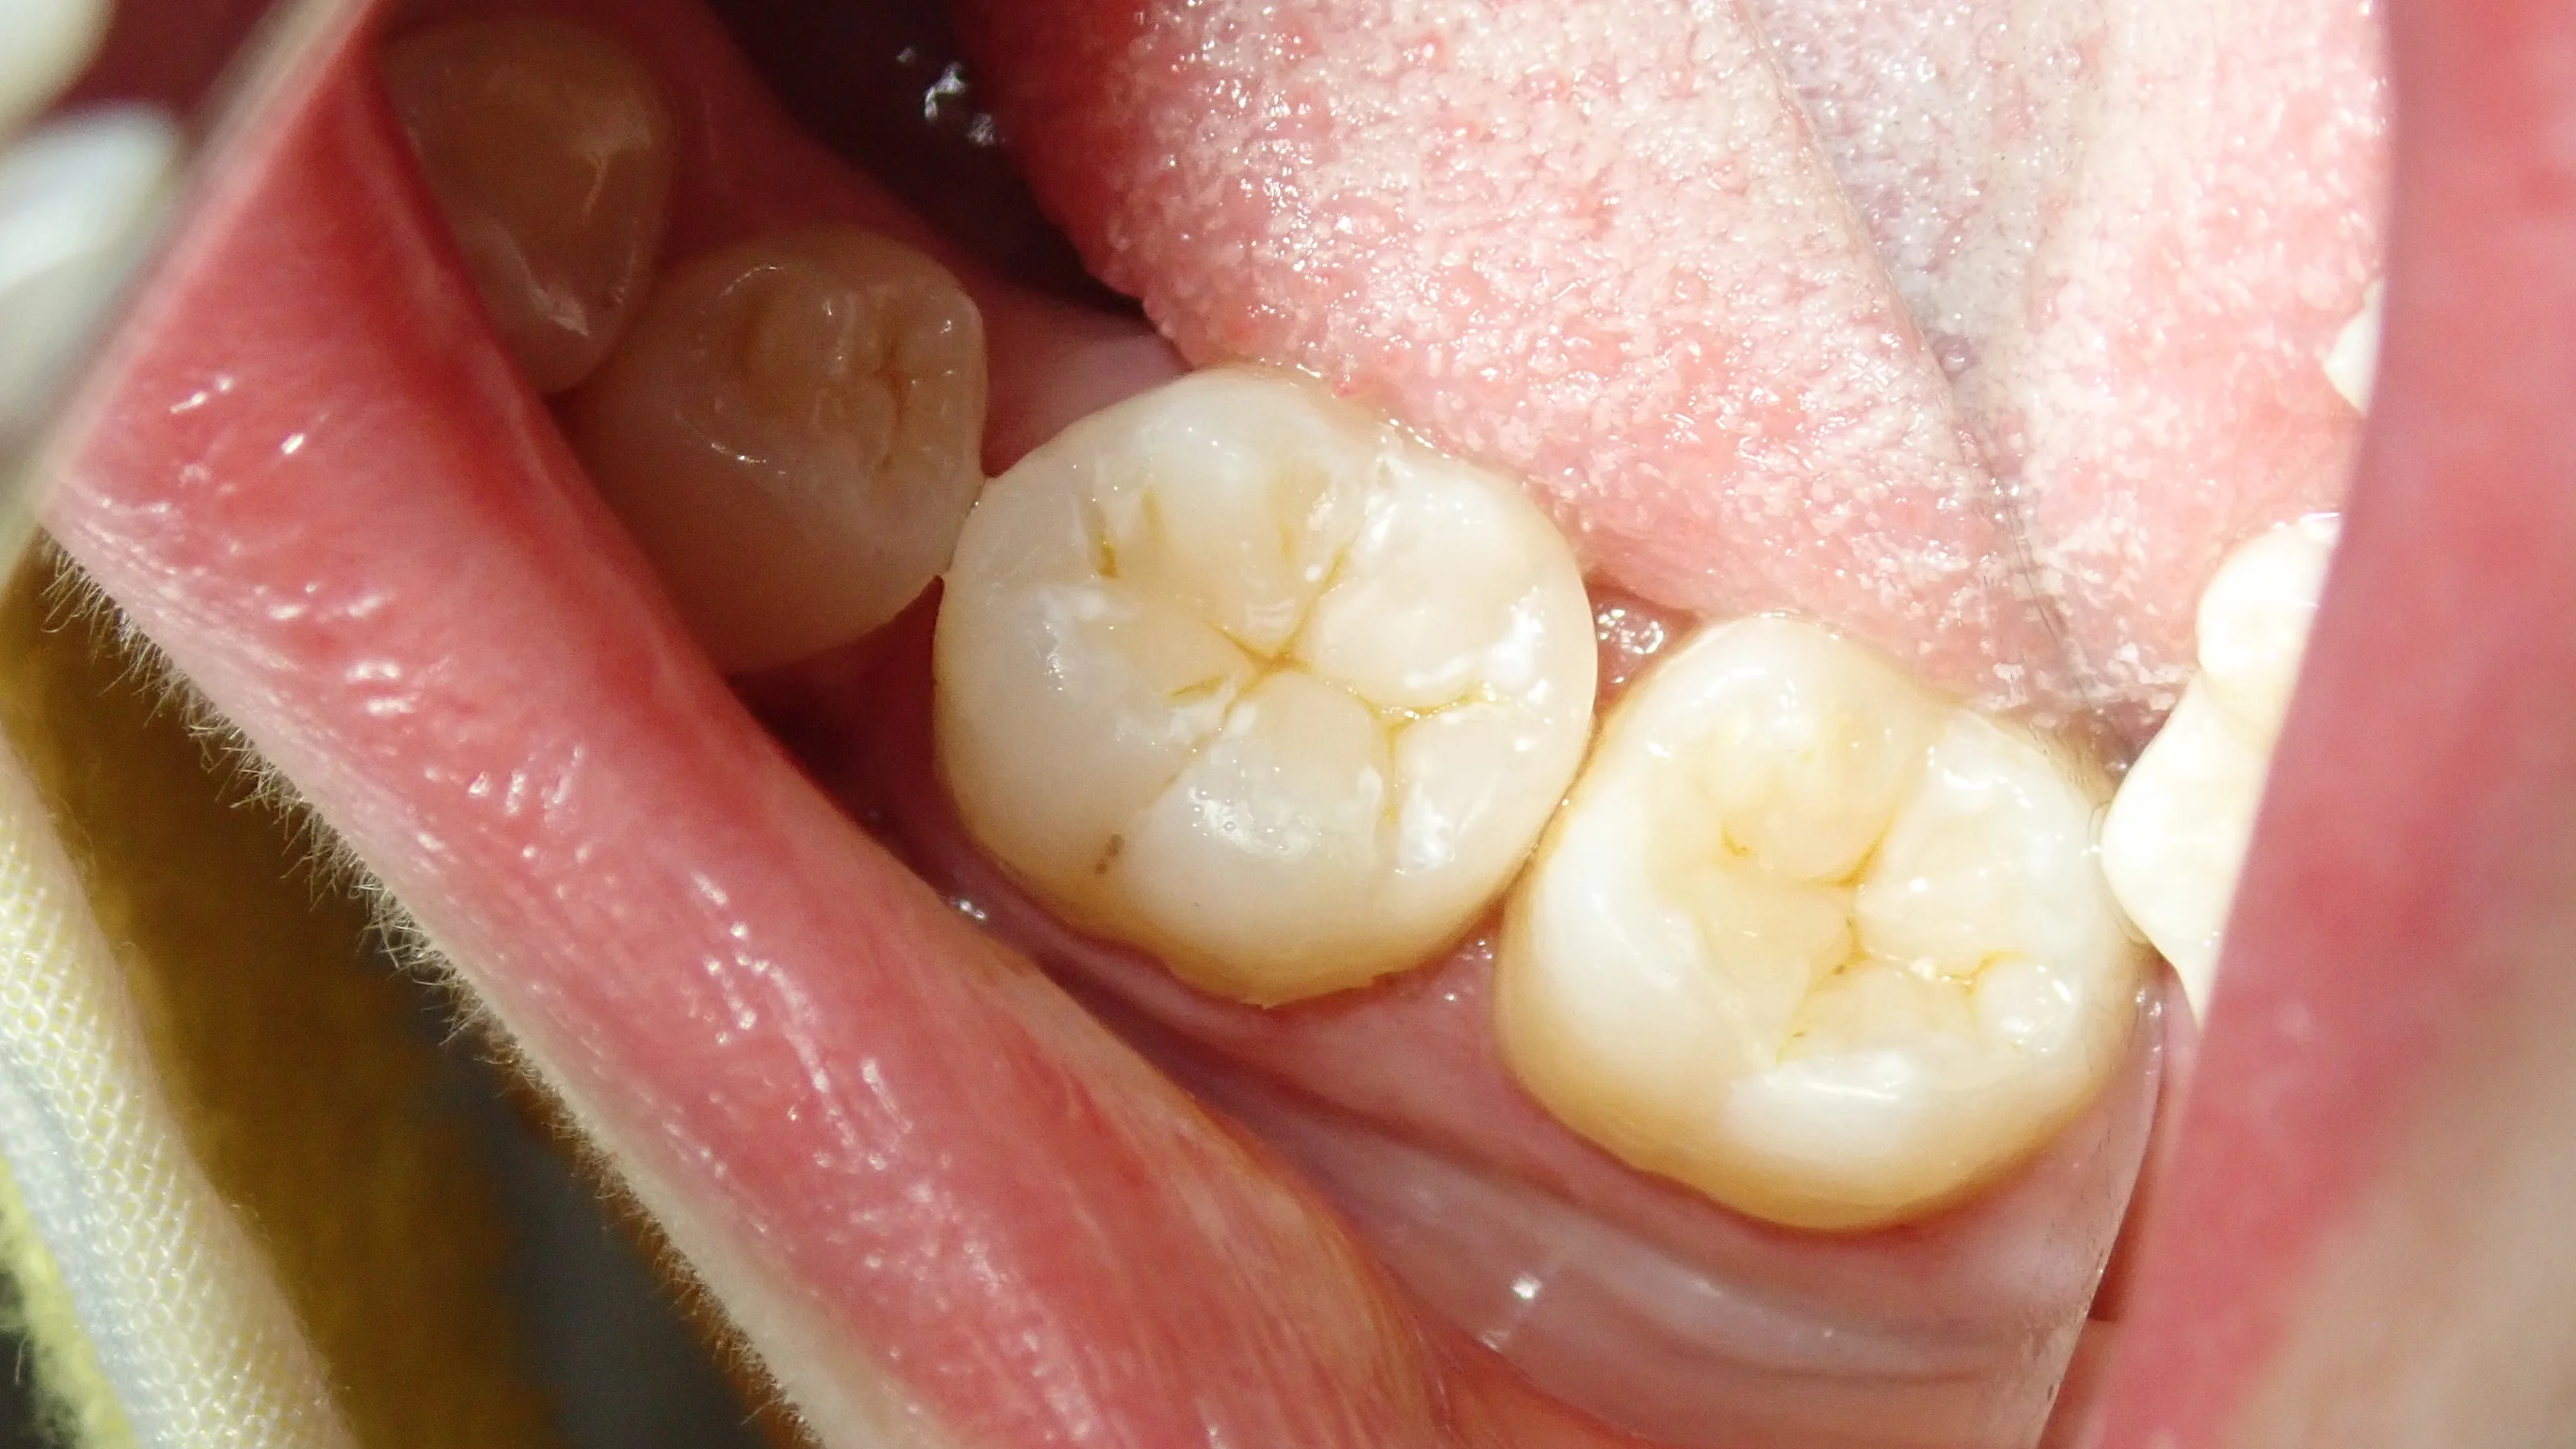

そして、詰め終わったのがこちら

スペースが非常に大きかったため、半ば無理矢理スペースを埋めました。

歯科医療従事者の方なので、ブラッシングなどはしっかりと行ってもらえるでしょう・・・!

良好な結果を得ることができました。

しっかりと歯磨き・フロスなどを頑張って、なるべく長持ちさせていただきたいですね!